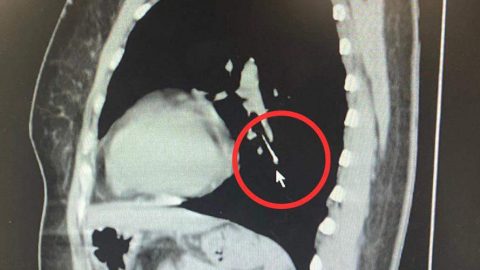

Postjung Plus